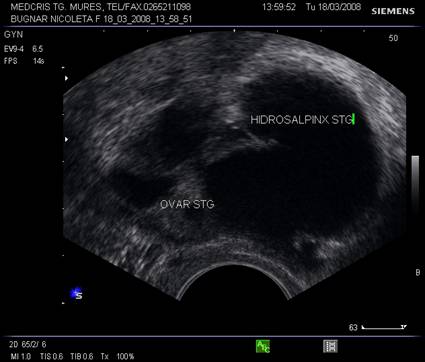

Trompele uterine normale nu pot fi identificate decat la emergenta, intr-o sectiune coronala la nivelul fundului uterin, ca o structura liniara hipoecogena.[6] Daca exista lichid liber in fundul de sac Douglas, partea pavilionara tubara poate fi evidentiata flotand. Trompele normale, cu lumen normal pot fi evidentiate cu agent de contrast instilat endocervical (de exemplu Echovist). Trompele cu continut patogen pot fi evaluate ecografic cel mai bine transvaginal.

Fig. nr. 404. Colectie anecogena in lumenul trompei .Hidrosalpinx ce inconjura ovarul omonim, se remarca peretele cudat al trompei cu continut lichidian.